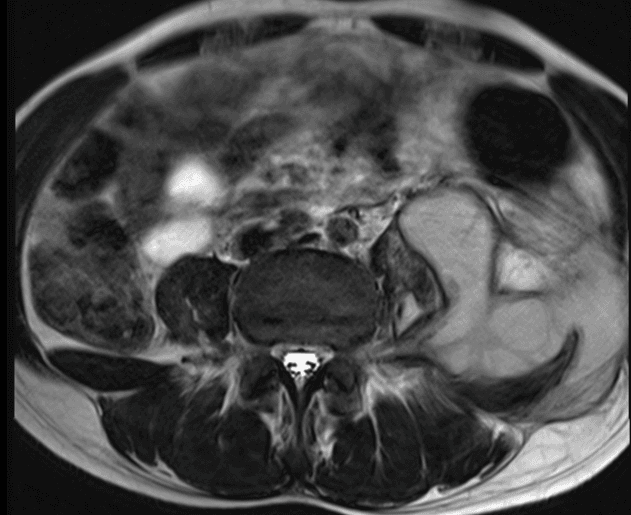

Paciente do sexo masculino, 28 anos, com dor lombar crônica agudizada após trauma direto.

Figura 3.